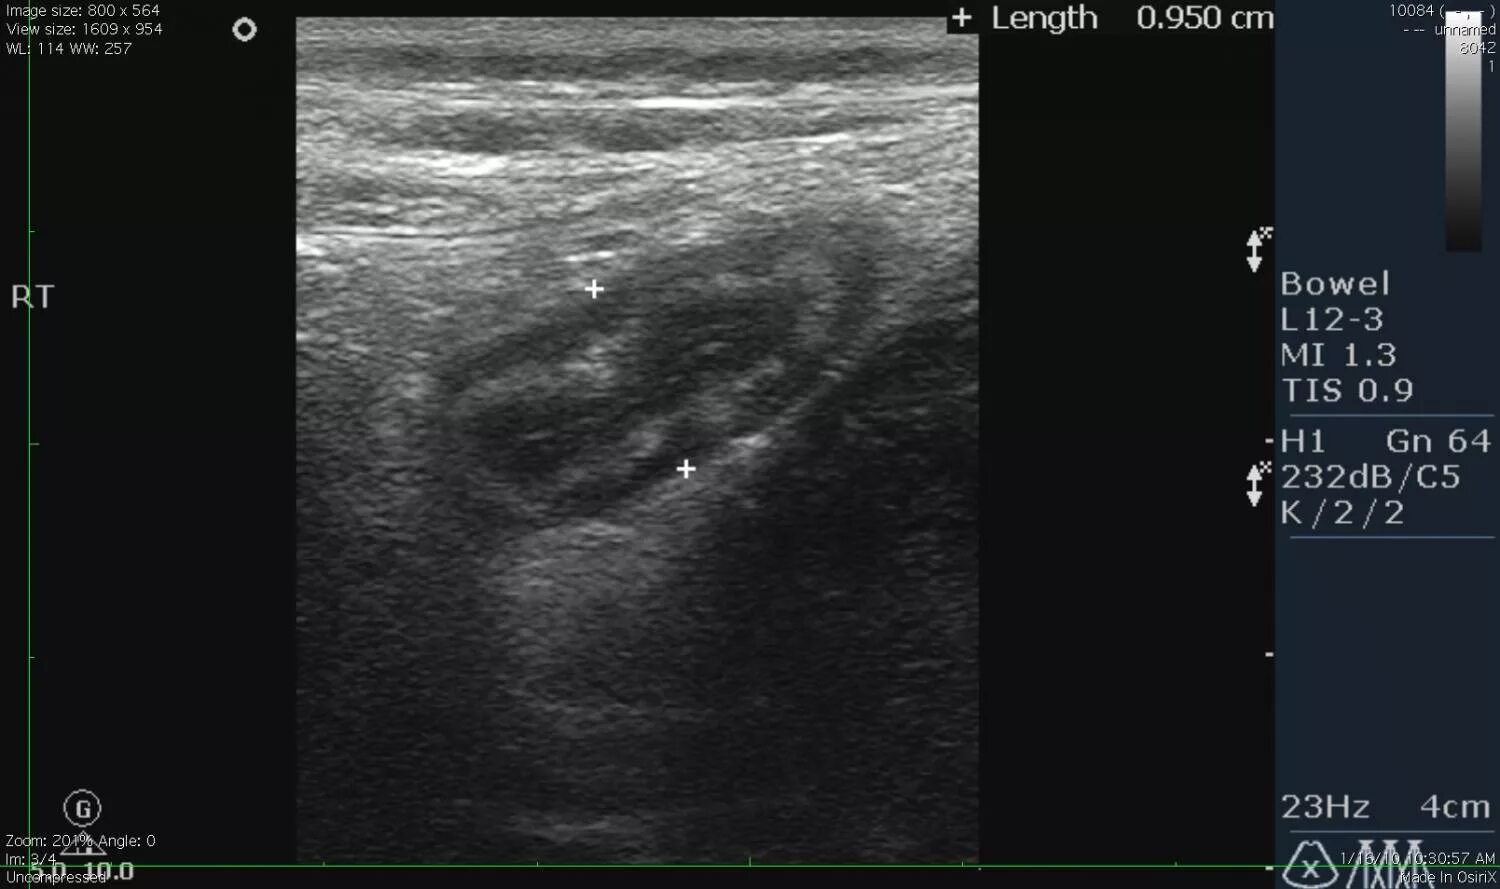

Какое узи при аппендиците